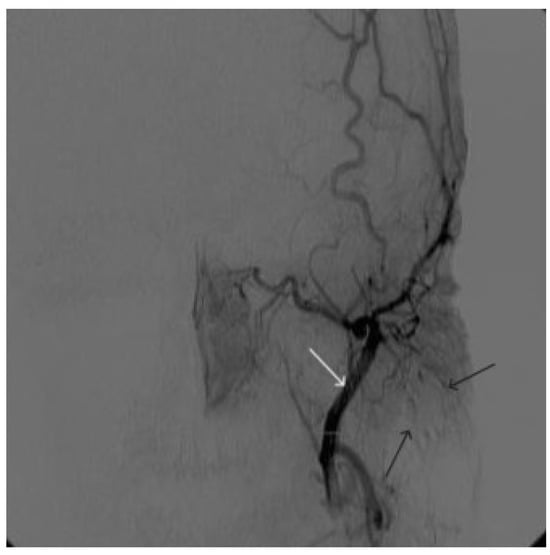

A 58-year-old male patient was admitted to the clinic complaining of a palpable formation in the left submandibular region. When angiography was performed, the filling of the vascular network of the tumor of the left submandibular region from the branches of the left occipital artery, as well as the muscular branches of the left vertebral artery, was noted (Figure 11). The patient underwent intravascular embolization of the paraganglioma with 7.5 mL of non-adhesive composition ONYX18 (Figure 12 and Figure 13). The vascular network supplying the paraganglioma was partially switched off (Figure 14). There were no complications. The mRs score at discharge was 1.

Figure 14. Digital subtraction angiography from the left common carotid artery: (a) direct projection, (b) lateral projection (white arrows indicate the guiding catheter in the left external carotid artery, black arrows indicate the boundaries of the embolized paraganglioma).